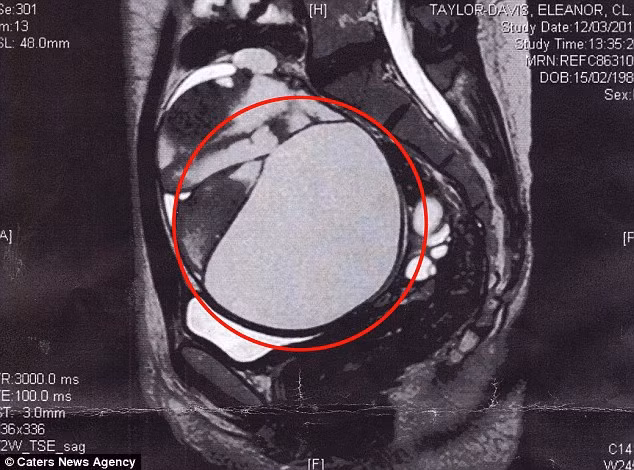

(Kiến Thức) - Cô gái trẻ đã phát hoảng khi được biết mình có một khối u khổng lồ 16cm trong buồng trứng.

Siêu âm cho thấy khối u có kích cỡ đến 16cm trên buồng trứng. Nó chèn ép cả vào các cơ quan nội tạng khiến cô đi tiểu khó và đầy hơi.

May mắn thay, bác sỹ phẫu thuật có thể loại bỏ khối u ung thư chết người này mà không cần xạ trị. “Khi khối u được lấy ra khỏi cơ thể, nó rất lớn và kỳ lạ. Tôi còn không thể tin được nó đã tồn tại trong cơ thể mình”.